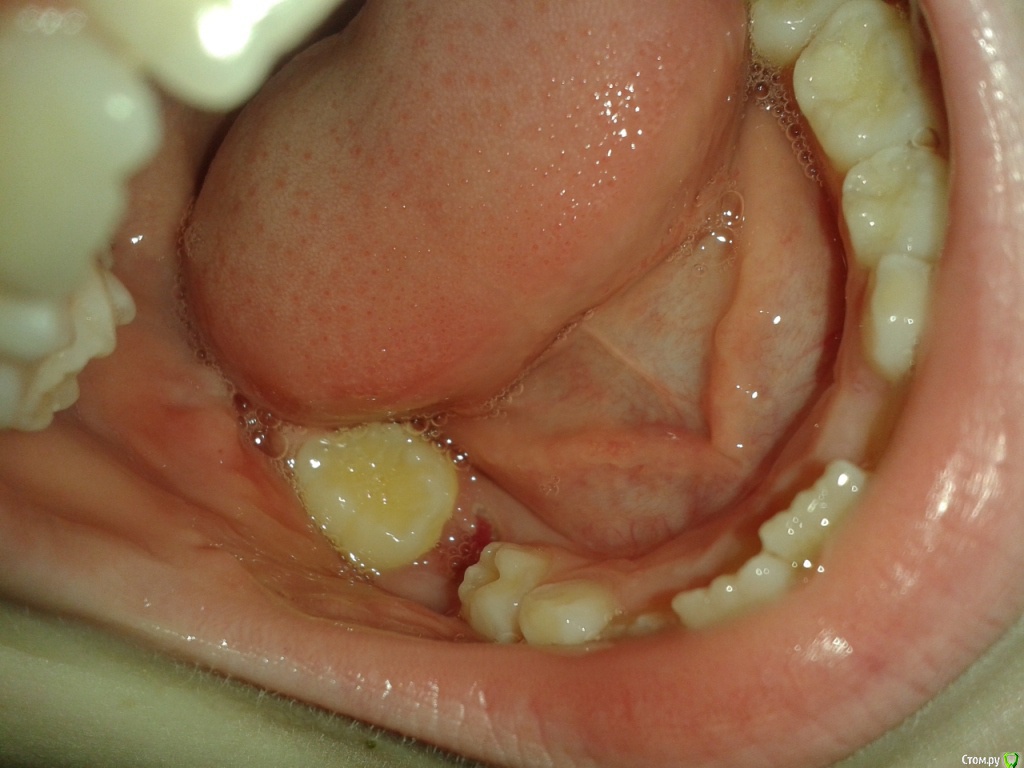

Через год начал прорезываться зуб, стоящий рядом с пролеченным. Прорезался и… наклонился. Теперь он ушел в наклон с одной стороны, закрывая при этом часть поверхности 5-ки. Наплыла десна, но не критично. С одной стороны зуб полностью вырос, с другой – в десне.

Обратились к терапевту. В лечении зубы не нуждаются, но высказала мнение, что нужно показаться ортодонту. Объяснила нам ситуацию: зуб вскоре закроет непрорезавшуюся 5-ку, и постоянный зуб под 5-кой не прорежется.

Пластинка должна выправить наклон. А дальше? Нам еще 5 лет ждать, так как ребенку недавно исполнилось 7 лет, зуб под 5-кой прорежется к 11-12 годам. 1,5 года ребенок относит пластинку. А если зуб наклонится опять? Что его будет удерживать? В ответ получаю второй вариант развития событий: после того, как наклон ликвидируется, нарастить зуб пломбой, но насколько это будет возможно, спрогнозировать трудно, однако, во время ортодонтического лечения будет требоваться коррекция десны лазером (будут удалять наросшую десну, чтобы открыть зуб). То есть получится ли свободное место занять пломбой, еще неизвестно. Но такой план, по ее мнению, конечно, предпочтительнее.

Под 5-кой зуб просто так не прорежется, потребуется хирургическое лечение. Это пугает, если честно.

Прилагаю снимки. Один до того, как прорезался наклоненный зуб. Второй - после его прорезывания и лечения зуба с анкилозом. Прошу прощения за качества некоторых снимков.